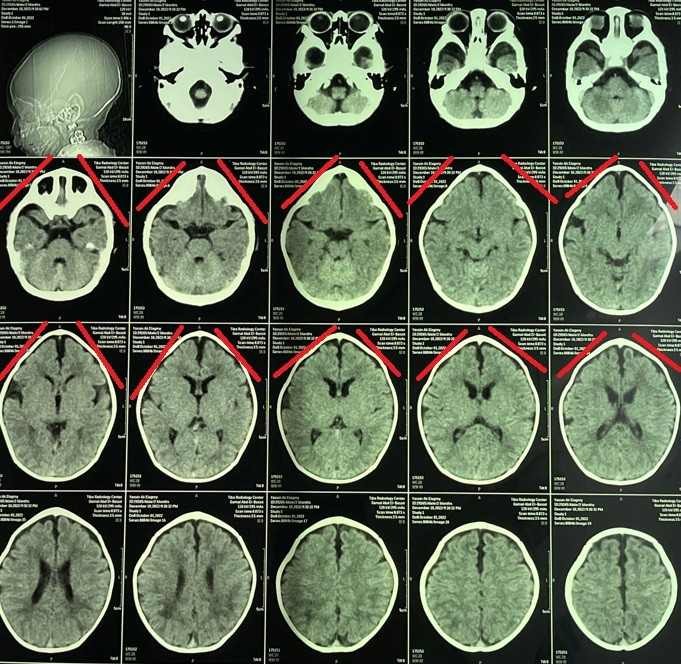

تم إجراء جراحة تقويم ناجحة لطفل يبلغ من العمر شهرين كان يعاني من حالة تعرف باسم "الرأس المثلث". هذا النوع من التشوهات الجمجمية يؤدي إلى ظهور الرأس بشكل مثلثي مع وجود نتوء بارز في الجبهة. الهدف من الجراحة كان تصحيح شكل الجمجمة لضمان النمو الطبيعي للدماغ وحماية الطفل من المشاكل المستقبلية.

• تخطيط دقيق مسبق باستخدام التصوير ثلاثي الأبعاد